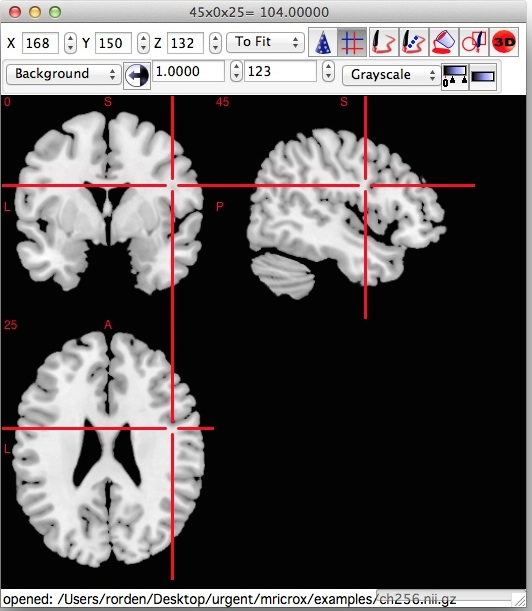

NTRC 团队还开发了 MRICron 软件,这是一款 NIfTI 格式的看图软件,而且它可以方便地调用 dcm2niix 进行图像转换。dcm2niix 的出现使得神经影像学数据的转换和处理更加高效、准确和便捷。

图形界面版需要先下载 MRICron。在上图左边设置好输出文件的命名格式,输出文件夹等参数,把dcm文件夹拖到右边空白处即可完成转换。

MRICron的下载链接,软件示意图👇